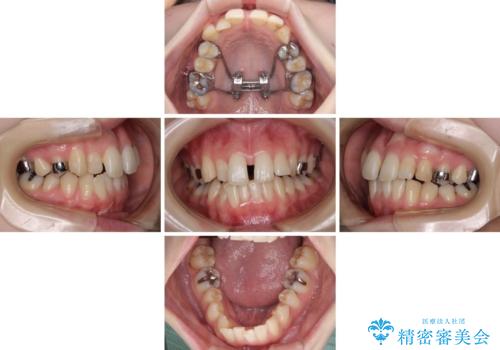

短期間での治療 急速拡大装置を併用したワイヤー装置による矯正治療

- 前歯のデコボコをクロスバイトを気にして来院された患者様です。

上顎骨の横幅が狭く、上下ともに内側に倒れ込んだ混み合った歯列となっていました。

急速拡大装置により上顎骨を側方に拡大し、ワイヤー装置により歯列を整えることとしました。

矯正治療後には、目立つ銀歯と隣接するむし歯をセラミックインレーにて修復治療することとしました。

左右ともに奥歯の咬み合わせには大きな問題がなく、窮屈な歯列を解決すれば歯列を整えることできたため、僅か1年で終えることができました。